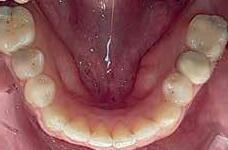

Non extraction treatment, with mesial root movement and protraction of the mandibular second and third molars in order to close the residual space, create a solid contact between the mandibular second molar and second premolar without the need for prosthetic dental implant or crown. This option would require longer orthodontic treatment time with extensive follow up visits, however no extra cost is allocated for surgical and prosthetic procedures. (Figures 1 and 2)

Bonding: Genius Passive self ligation ( MEM Corporation, Sweden Taiwan) with 14 NiTi (Thermal ultra) engaged. First molar bondable tube with a built in long extended hook that reached the level of the furcation to apply the force close to the center of resistance of the second mandibular molar.

April 2021:

- 18 NiTi Thermal ultra

June 2021:

- 18*25 NiTi Thermal ultra

July 2021:

- Short head Mini-screw 1.6 diameter, 8 mm length Titanium alloy (Absoanchor®) palced between the mandibular first Premolar and canine at the junction between attached and movable mucosa in a 45 degrees inclination.

- Lower wire: 16x25 stainless steel wire

- Connecting first molar hook to the micro-implant with a chain generating about 200g of force

- To avoid irritation of the cheek when in contact with the miniscrew head, a light cure silicone material was applied to cover the chain and the mini-screw all-together (Softflow®).

For almost 8 months, during the Covid pandemic, the patient was unable to present to the clinic. The work was resumed in March 2022. It was decided then to segment the appliance, including third molar to canine. The 16x25 SS wire was replaced with 17X25 S.S in the lower arch to increase the rigidity of the wire given the short span available.